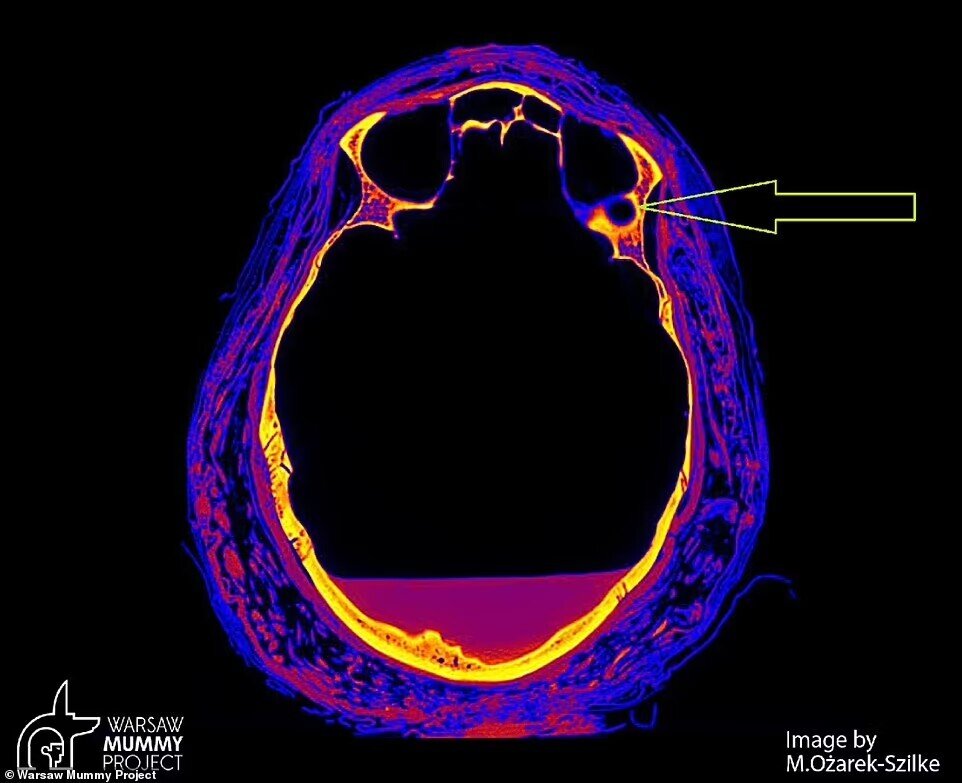

به گزارش 9 صبح به نقل از دیلیمیل پژوهشگران در لهستان که جمجمه یک مومیایی باستانی مصری را اسکن میکردند، نشانههای غیرمعمولی را در این استخوان شناسایی کردند.

تصاویر منتشرشده بوسیله «پروژه مومیایی ورشو» (WMP) در لهستان نشان میدهد که جمجمه این زن دارای ضایعاتی است که با بیشترین احتمال ناشی از تومور هستند و نقایص بزرگی که در بخشهایی از این استخوان مشاهده میشود، معمولا در جریان عملیات مومیایی کردن ایجاد نمیشوند.

پروفسور رافال استک از دپارتمان سرطانشناسی دانشگاه پزشکی ورشو که با کارشناسان در WMP همکاری دارد، میگوید: «ما تغییرات غیرمعمولی در استخوانهای نازوفارنکس یافتیم که بر اساس نظر کارشناسان مومیایی در روند مومیایی کردن ایجاد نمیشود. از طرف دیگر، نظرات رادیولوژیستها بر اساس توموگرافی کامپیوتری نشاندهنده احتمال تغییرات توموری در استخوان است.»